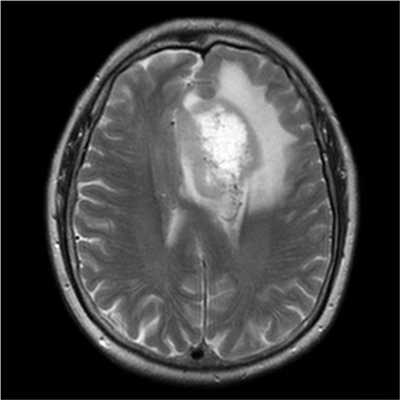

Злокачественная опухоль на МРТ

Злокачественные опухоли характеризуются инвазивностью, то есть врастанием в здоровые ткани, поэтому контуры таких образований нечеткие и неровные, а потому достоверно определять границы таких опухолей довольно сложно. Кроме того, структура злокачественной опухоли часто бывает неоднородна за счет распада (некроза), кровоизлияния и коллоидной дегенерации. Вокруг злокачественной опухоли, как правило, выявляется выраженный перифокальный отек, который может приводить к смещению срединных структур головного мозга и появлению аксиальной дислокации. Также могут быть выявлены признаки метастазирования.